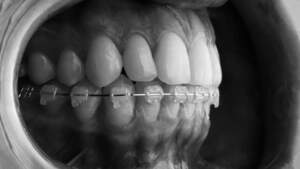

裏側の矯正中の歯の裏側を歯科用鏡で映したイラスト

裏側矯正は舌側矯正、リンガル矯正とも言います。歯の裏側にブラケットとワイヤーを付けるため外からは見えない矯正方法で、「矯正をしていることを知られたくない」「目立たずに歯列矯正をしたい」という方におすすめです。

フルリンガルは上下全ての歯の裏側にブラケットを装着し、ワイヤーを通して歯を移動させる矯正方法です。

フルリンガルの最大のメリットは、歯の裏側に付けるため矯正装置が目立たない点です。お仕事で装置が目立つと困るという方や歯列矯正をしていることを周囲の人に知られたくないといった方には、フルリンガルがおすすめです。裏側につくことにより、今まで無意識に舌で歯を押していた方も改善することができます。この無意識に舌で押してしまうという癖は歯並びを悪くする原因の一つであり、この癖の改善がされると言うことは、装置が外れた後の後戻り防止にもつながります。

裏側矯正で使用する歯の裏側にブラケットとワイヤーを装着した歯のイメージ